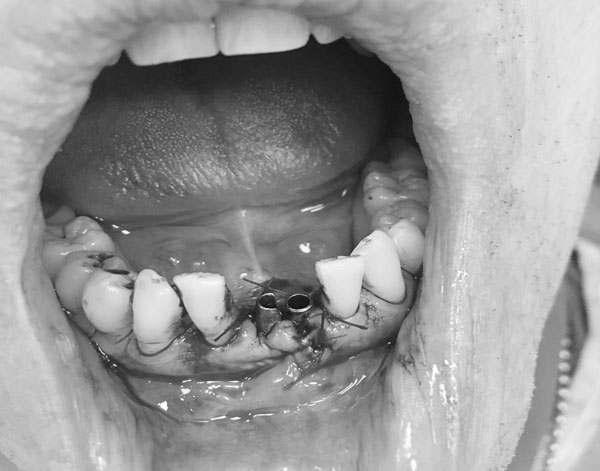

Рис.1 Этап экстракции зубов 31,41 с подвижностью 3-4 степени

Обязательной тактикой немедленной имплантации следует считать атравматичную экстракцию зубов во фронтальном отделе, которая производится с помощью тонких элеваторов. Осуществление люксации при данном оперативном подходе возможно только   с медиальной, дистальной и оральной стенок альвеолы во избежание перфорации вестибулярной стенки апикальной частью имплантата (Рис.1). Даже при остеоинтеграции имплантата при повреждении вестибулярной стенки эстетика будет нарушена. Поэтому после проведения немедленной имплантации 3D-томография снова является идентификатором показателей инклинации имплантата, глубины его погружения в губчатый слой, выявления дефектов костной структуры (Рис.2,3,4,5,6).